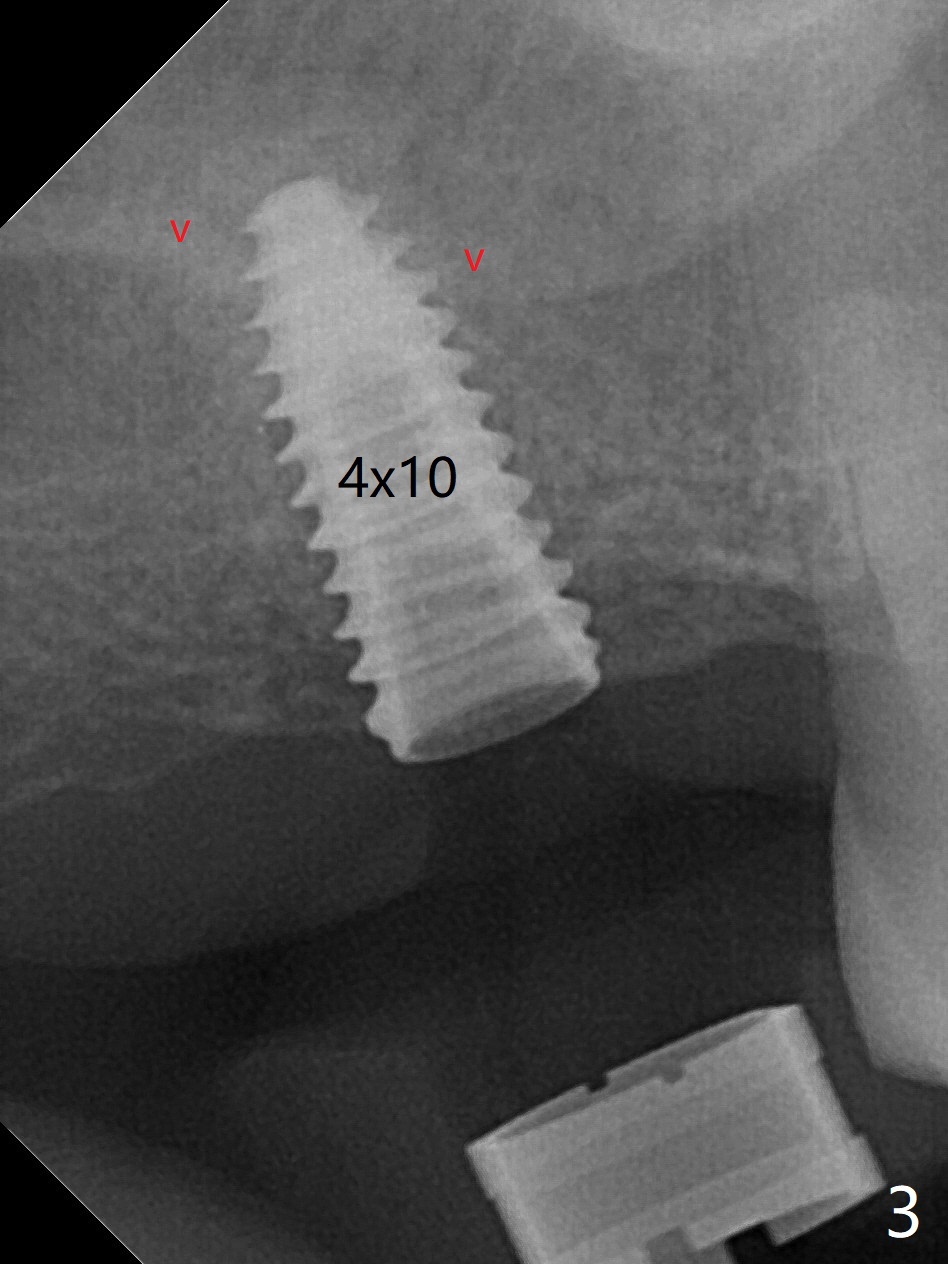

尽管事先准备15号刀片,看到完整2号牙牙槽嵴就舍不得切开。放置以前导板(用于即种),用软组织环形刀做个记号,接着用活检环形刀切取钻洞表面软组织,保存于PRF液体中。术前CT显示3号牙上方粘液囊肿(图一:*),而2号牙上方窦膜薄,总之两者都不好惹(容易感染,窦膜破),提升需要特别小心。完成初步钻洞后,使用17-19毫米长的DIO圆钻,放置粘性骨粉,使用4.5x10毫米报废植体进行提升(到第一横线),结果窦底没有穿(图二:红箭头)。接着使用尖头钻头从原来2.2x5.3毫米一直到3.5x10毫米,几乎每使用一个钻头后都检查窦底完整性,再放置骨粉,使用4.0x10毫米植体提升(到第二横线),好像穿过窦底(图三)。再加骨粉,使用4.5x10毫米植体扭力底,最后放置PRF膜,很难塞入上颌窦,结果只能从钻洞上端近中很小裂口塞入,植入5x8.5毫米正式植体(图四),上颌窦里骨粉呈蘑菇状(*)。临床检查腭侧(P)植体牙槽嵴下,其余骨壁难于判断。而咬翼片却显示植体颊侧(B),腭侧均在牙槽嵴下(图五)。为了减少术后骨质吸收,放置愈合螺帽后(图六:S),植体表面添加骨粉(*),最终把保存的软组织放回原位(二期手术:减少上颌窦与口腔交通,感染),牙周胶水粘固(图七)。术后没有鼻出血。